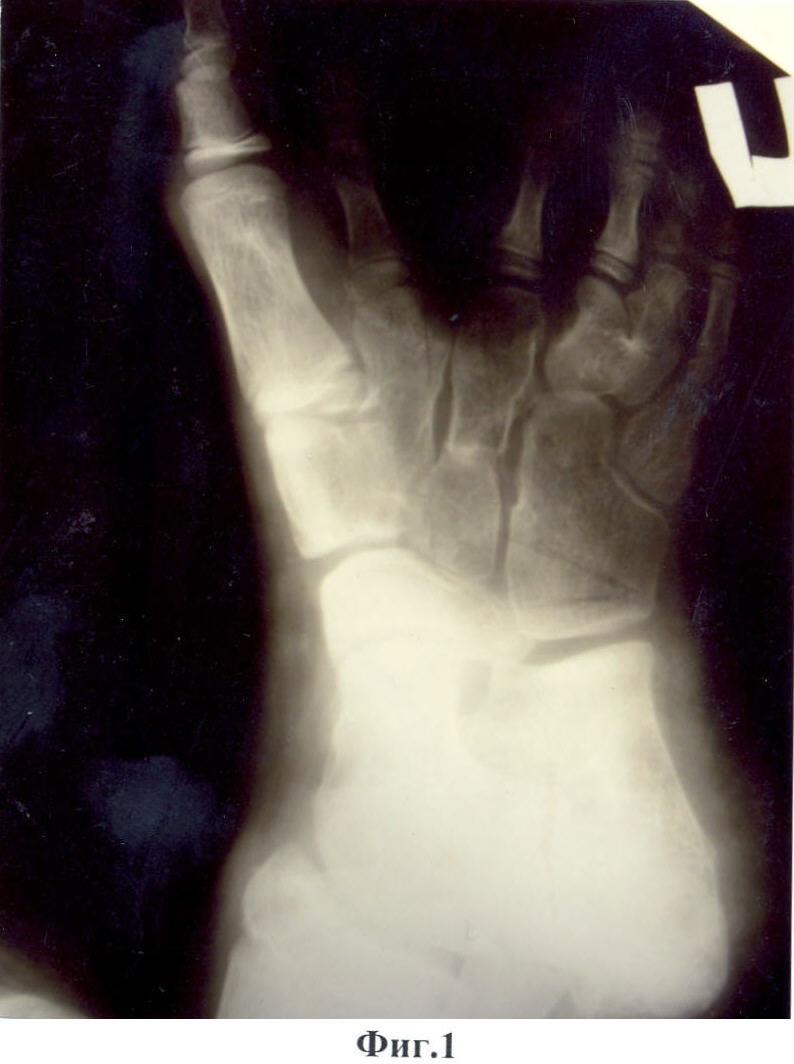

Предложенный способ иллюстрируют приведенные рентгенограммы и фотографии, где на фиг.1, 2 показан вид стопы до операции; на фиг.3, 4 – вид после операции; на фиг.5, 6 – снимок и фотография стопы через два месяца после операции.

Больной М-в, 12 лет. История болезни №6618. 11.12.2006 г. Поступил в отделение кисти «НИЦТ ВТО» с диагнозом: Сложное врожденное расщепление с элементами полидактилии, синостозом IV-V плюсневых костей и сверхкомплектом лучей обеих стоп (фиг.1, фиг.2).